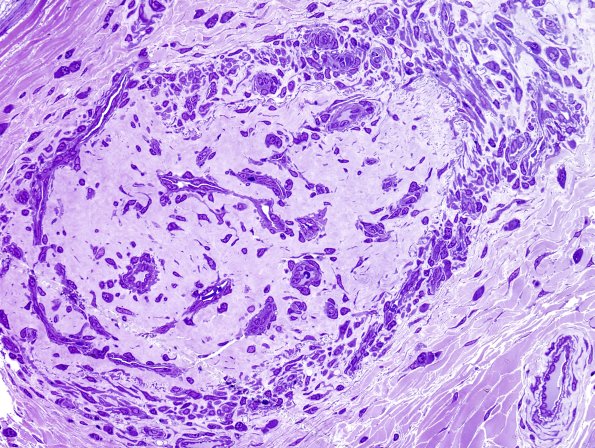

The epineurial vasculature is extensively involved. (Plastic sections) ---- Comment: In this case there is no definitive evidence of the role of CMV in the neuropathy in this patient and it may reflect a direct effect of HIV on the epineurial vasculature (still, however, representing an infectious process). Nonetheless, I wish we had performed CMV immunohistochemistry.